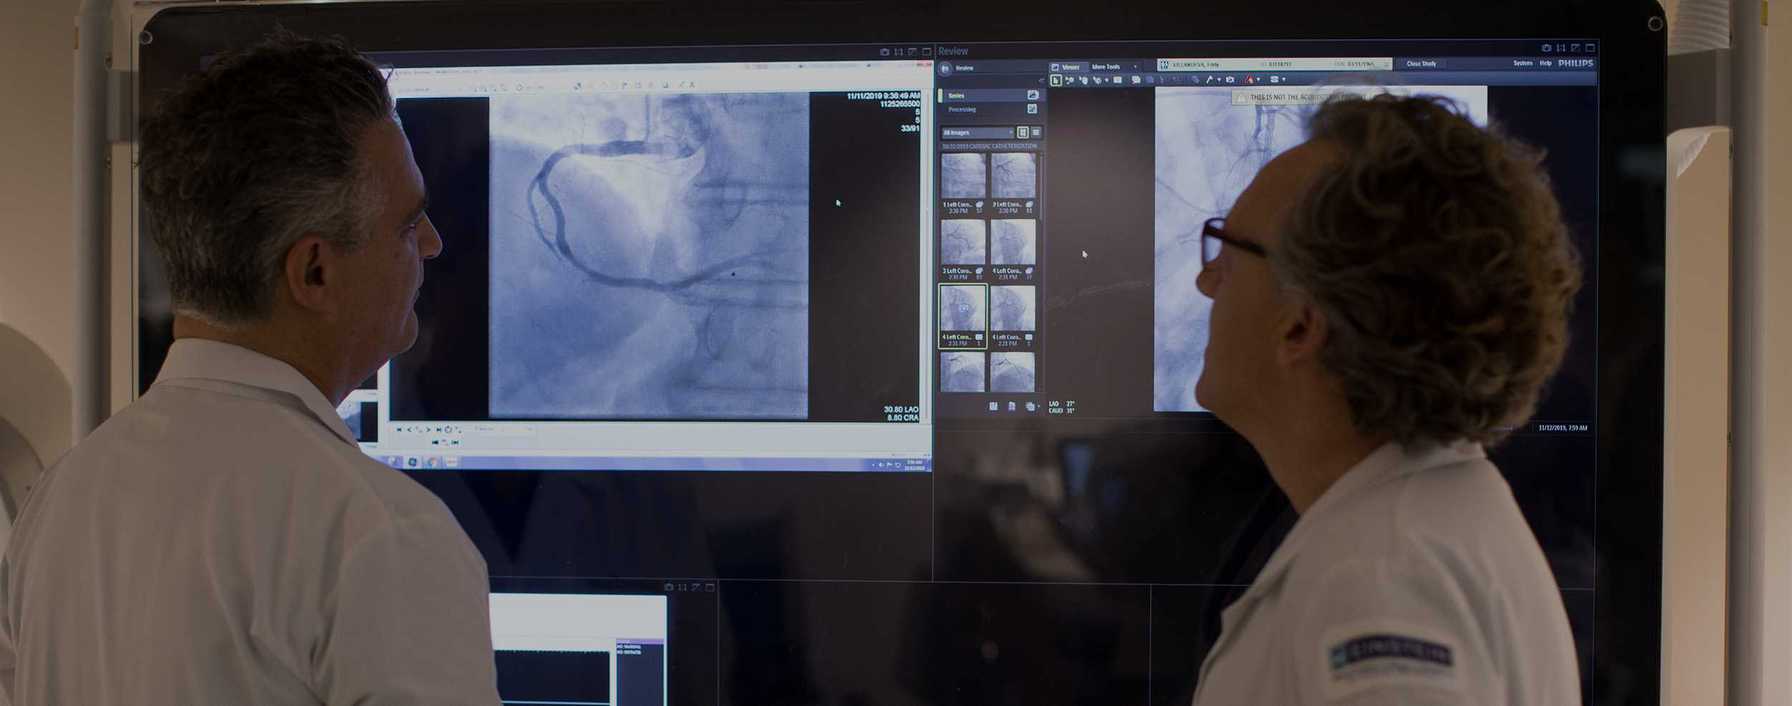

Montefiore Einstein Cardiology

In 2024, Montefiore Einstein Cardiology advanced its leadership in cardiac care and research, making groundbreaking strides in heart transplantation, structural valve interventions and arrhythmia management, while also expanding its state-of-the-art imaging program. This commitment to innovation, alongside significant contributions to scientific research and global education, underscores Montefiore Einstein's dedication to providing the highest quality of care.

Imaging